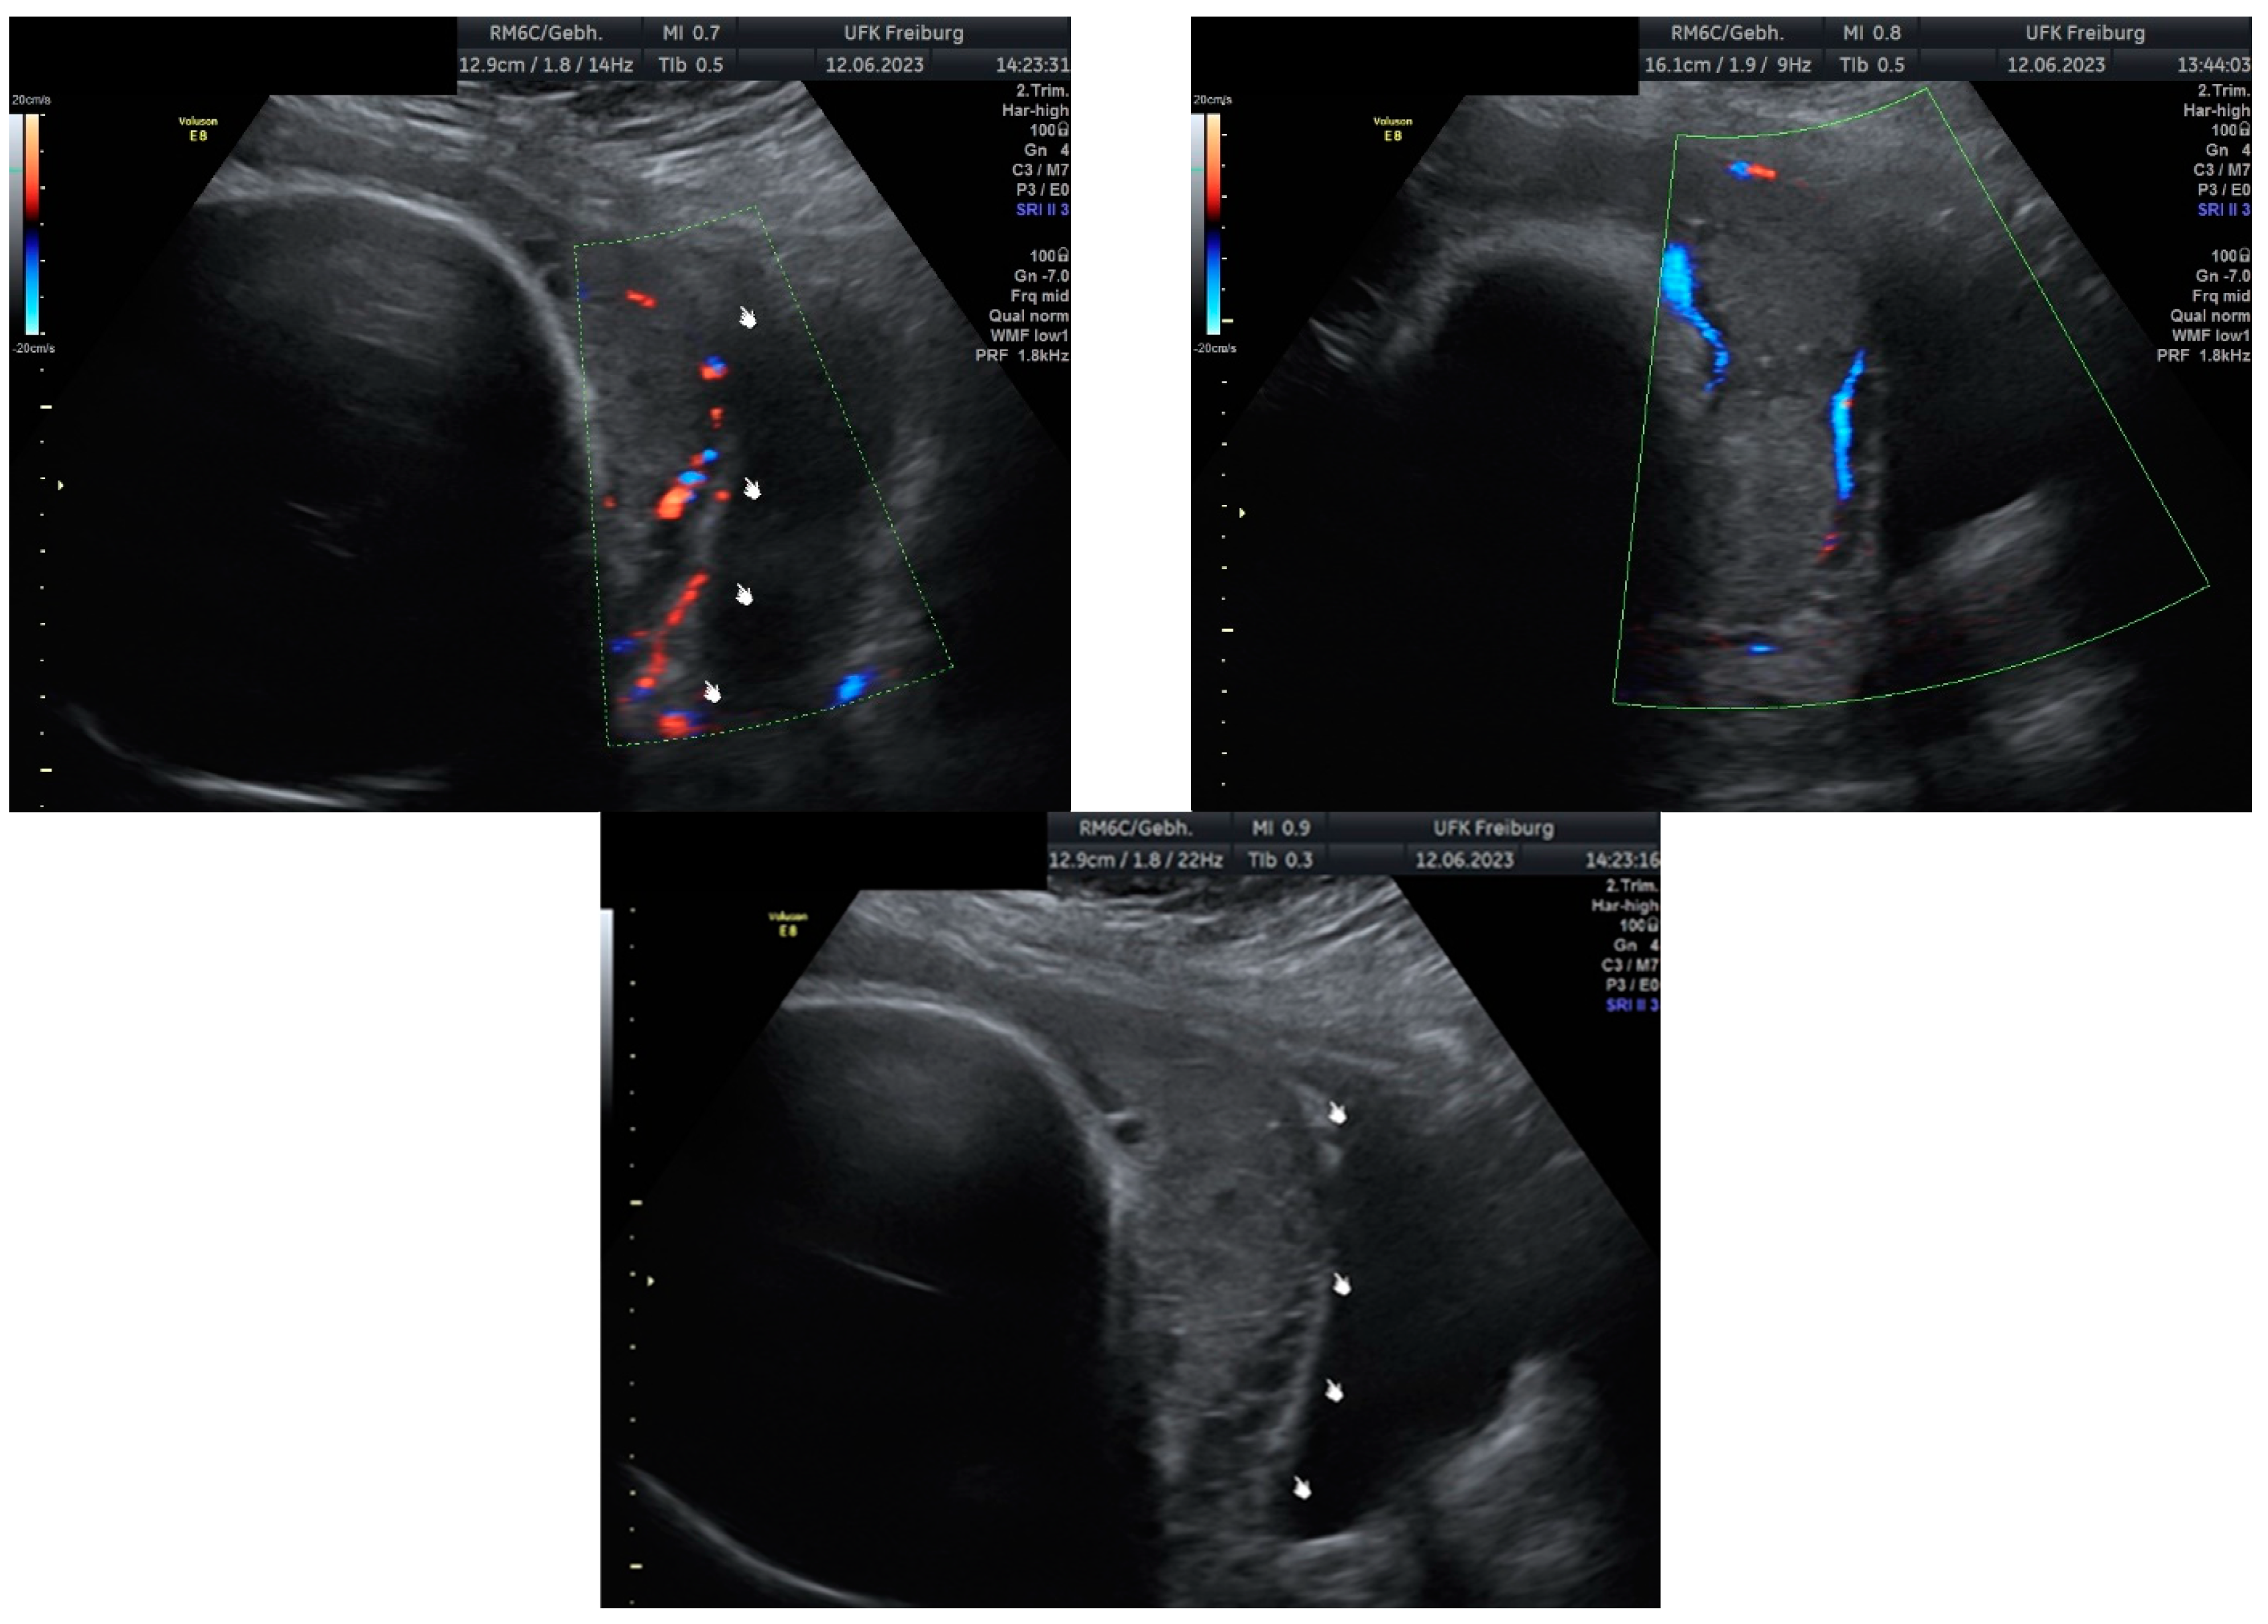

Sonographic findings (Figure 7):

Figure 7.

Revealed the following sonographic findings:

A very small barrier between the uterus and the bladder, with no recognizable

- myometrium in this area.

- Numerous blood vessels, most parallel and two perpendicular.

- Multiple placental lacunae confirmed by color Doppler.

Based on these findings, we planned an elective cesarean section at 35 weeks of gestation, combined with a hysterectomy due to the confirmed placenta increta and the high risk of significant bleeding. These findings were confirmed during the laparotomy.

Intraoperative findings (Figure 8):

Figure 8.

Depict the uterus during and after hysterectomy performed for placenta increta.